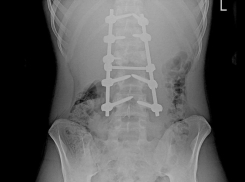

Общество Воронежские врачи вернули 16-летнему подростку возможность ходить после тяжёлой травмы

Минздрав поделился историей о реабилитации юноши